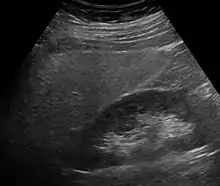

Imaging studies are often obtained during the evaluation process. Ultrasonography reveals a "bright" liver with increased echogenicity. Medical imaging can aid in diagnosis of fatty liver; fatty livers have lower density than spleens on computed tomography (CT), and fat appears bright in T1-weighted magnetic resonance images (MRIs). Magnetic resonance elastography, a variant of magnetic resonance imaging, is investigated as a non-invasive method to diagnose fibrosis progression.[30] Histological diagnosis by liver biopsy is the most accurate measure of fibrosis and liver fat progression as of 2018.[8] Conventional imaging methods, such as ultrasound, CT and MRI, are not specific enough to detect fatty liver disease unless fat occupies at least 30% of the liver volume.[31]